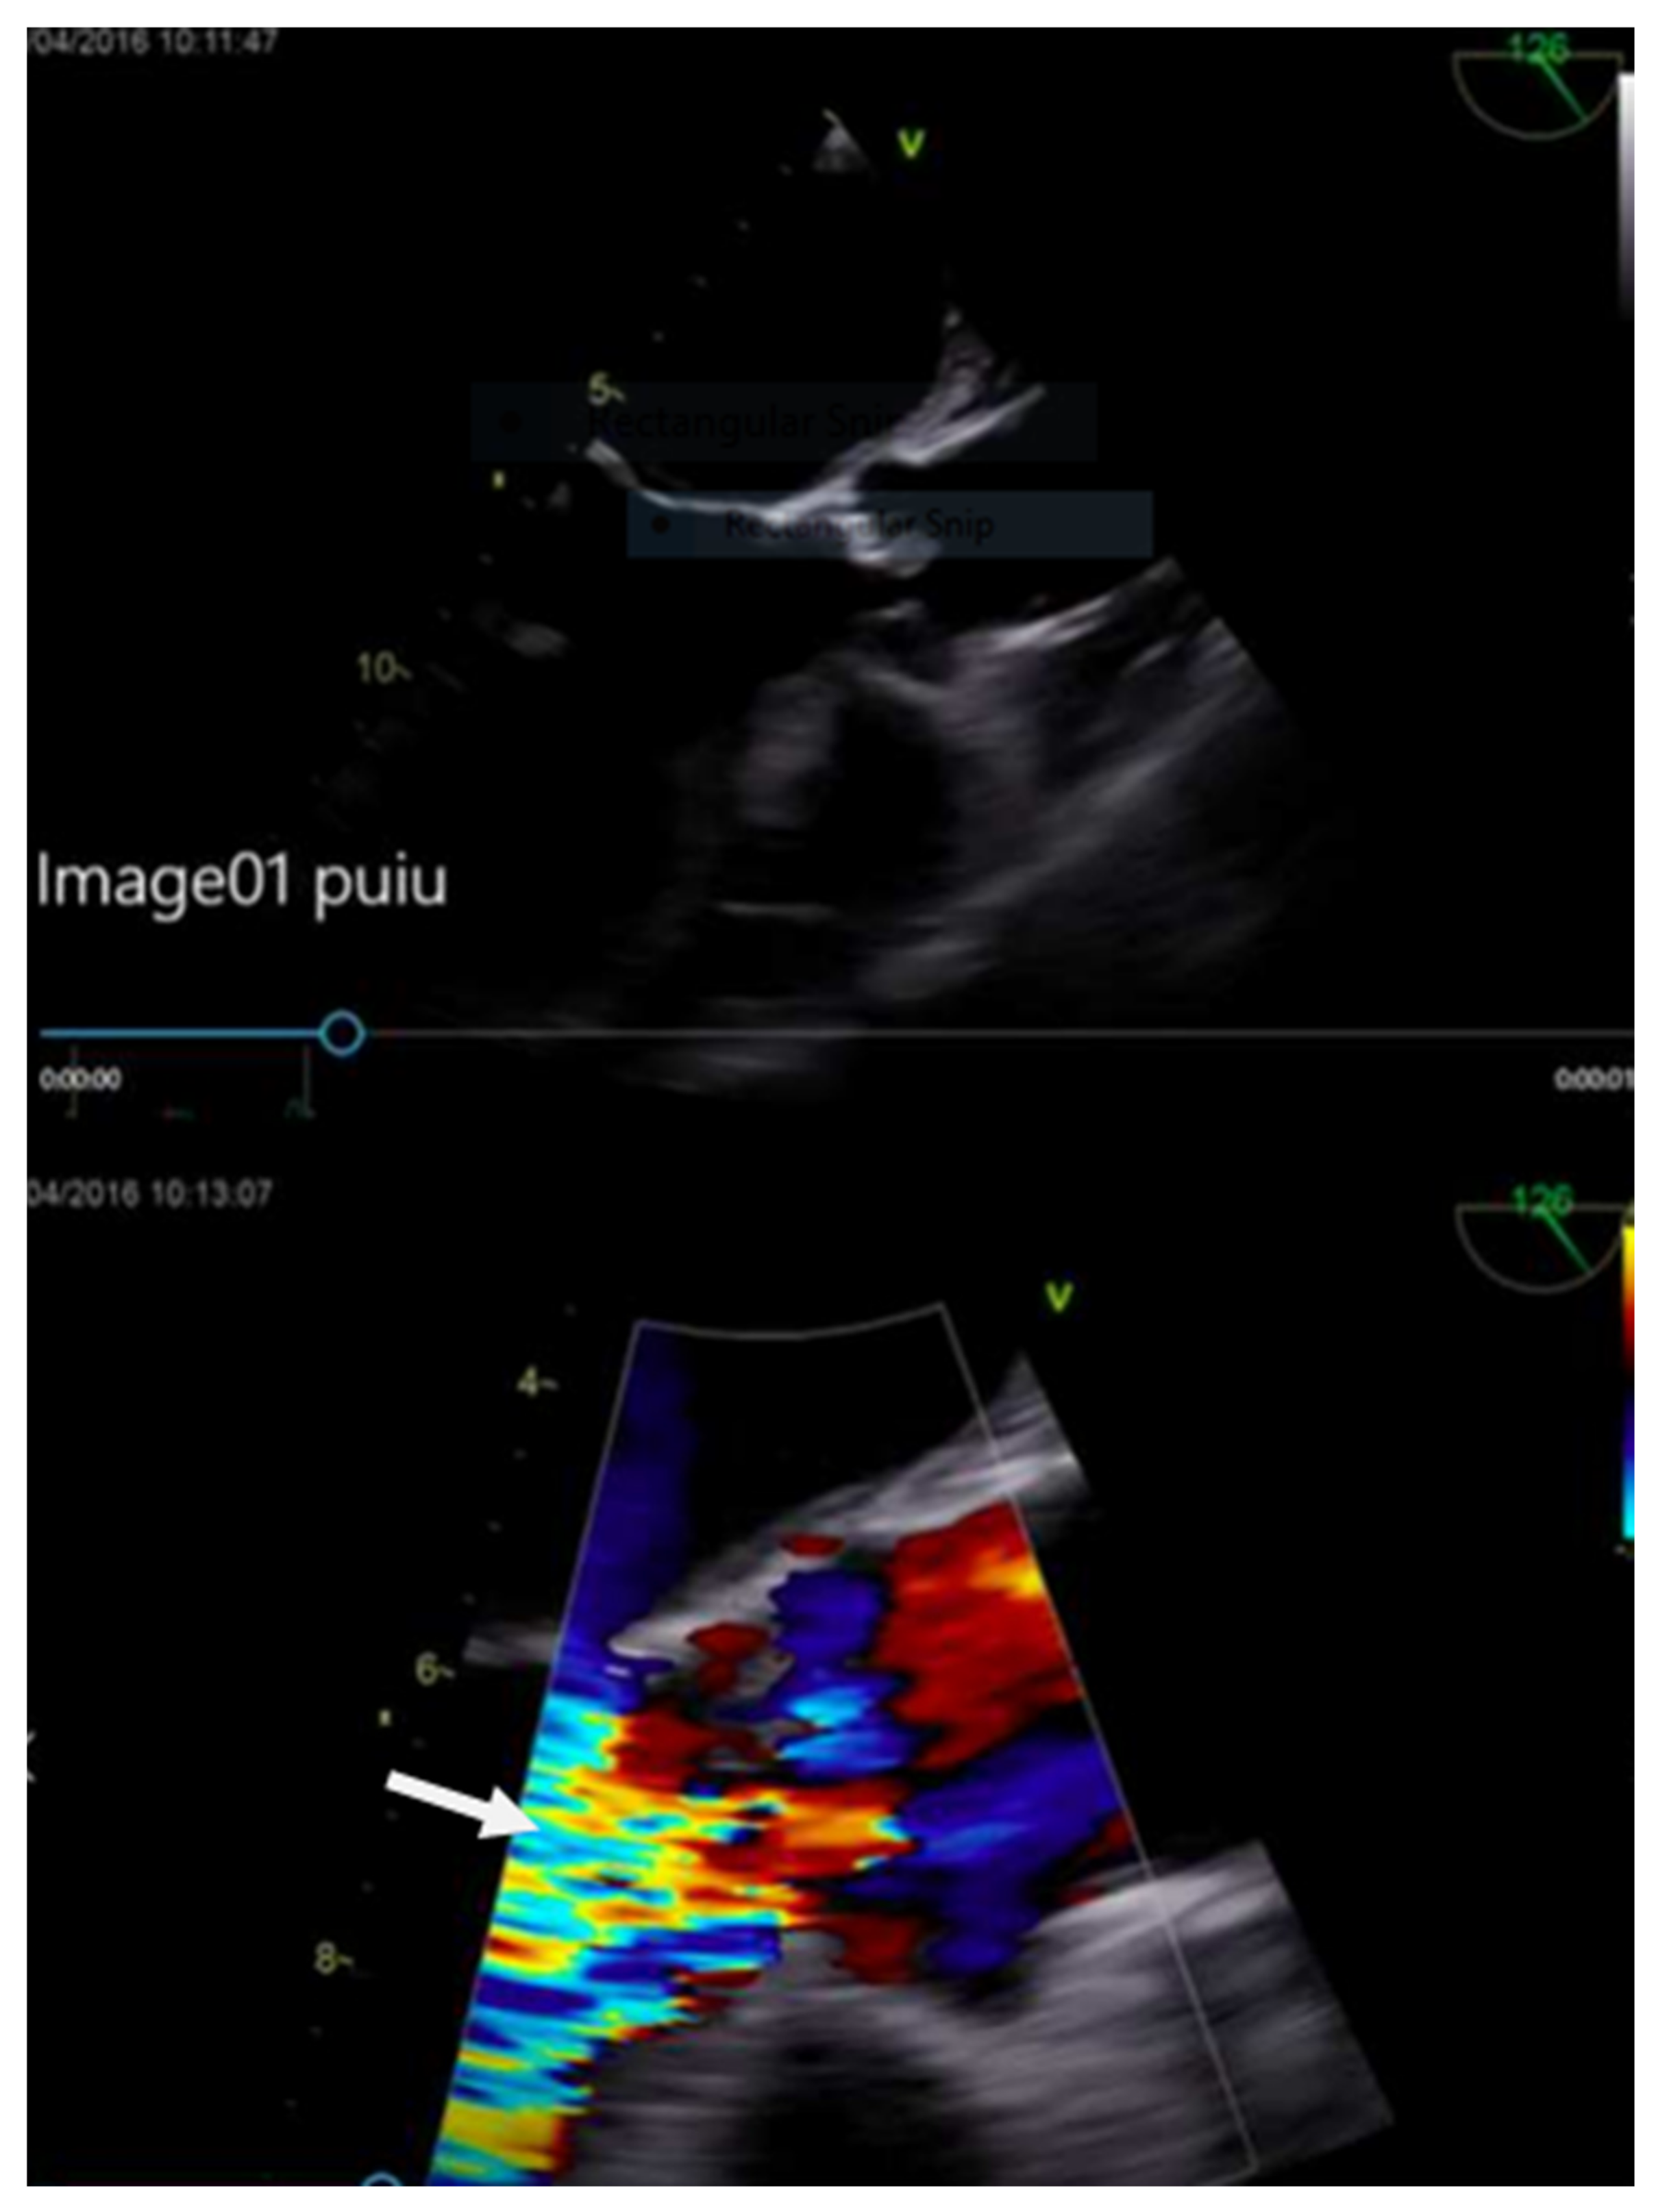

The transesophageal echocardiography (TEE) showed a hypokinetic anterior wall of the left ventricle with significant systolic dysfunction ejection fraction (EF) 38%. There was a perforated noncoronary cusp with severe aortic regurgitation and a large 20 mm vegetation (Figure 7). The calculated Euroscore II was 33.4%.

Figure 7. Echocardiographic image showing the aortic valve vegetation and aortic regurgitation.